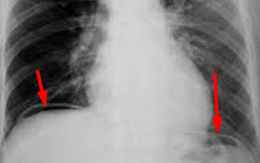

Lo lắng thi cử, cẩn thận bị thủng ổ loét hành tá tràng

Lo lắng về kỳ thi chuyển cấp, nam sinh lớp 9 bị đau bụng ở vùng trên rốn nhiều hơn trước. Sau ca học thêm buổi tối, em bị đau bụng dữ dội kèm sốt và được chẩn đoán viêm phúc mạc do thủng ổ loét hành tá tràng.